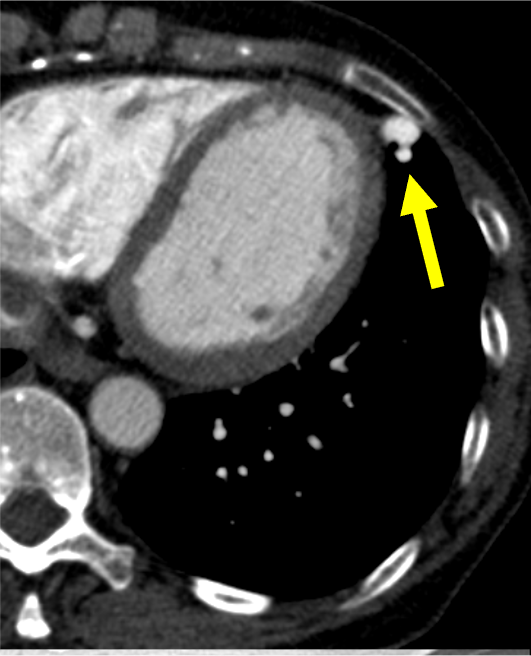

肺動静脈奇形は肺動脈・静脈が正常の毛細血管を介さずに短絡する血管奇形であり、肺動静脈瘻と呼ばれることもある。臨床症状としては低酸素血症や喀血、稀に血胸を示す。また、脳膿瘍や奇異性脳梗塞などの合併症を伴う可能性が知られている。しかし無症候性に肺結節として偶発的に指摘される例も少なくない。流入動脈、流出静脈がともに1本の場合をsimple type、複数の場合をcomplex typeと分類する。

造影CTでは肺動脈と同等の強い造影効果を呈し、単純CTに比して詳細な評価が可能となる。動静脈奇形の大きさ、流入動脈・流出静脈の数や吻合の位置をあらかじめ確認することで、治療計画に有用である。また、3D画像を再構成することでより立体的に形状を把握することができ、任意の方向から画像を観察することで塞栓時のアクセスルートを決定する一助となる。